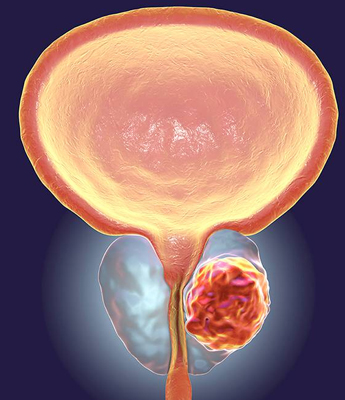

Prostate Cancer, a serious condition involving the development of cancerous cells in the prostate, is another critical concern. Regular consultations with a urologist are crucial for maintaining prostate health. Urologists provide valuable screenings, expert advice, and tailored treatment recommendations to address prostate disorders effectively. Early detection and management of these conditions are essential for preserving quality of life and ensuring optimal prostate function.